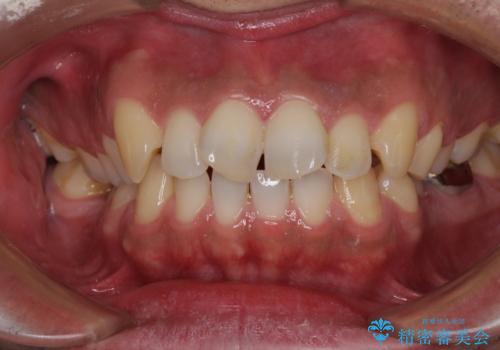

- 前歯が捻れており出っ歯であることを気にして来院された患者様です。

1度の来院で進められる限りの処置を行ったため、4回の来院で僅か1ヶ月で治療を終えることができました。

気になっていた前歯の問題が解決し、患者様には大変満足していただきました。